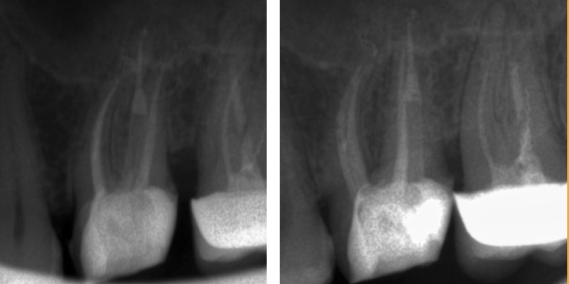

Instrumentele fracturate în canalele radiculare pot să constituie alte obstacole în calea îndepărtării bacteriilor, de aceea trebuiesc îndepărtate (Fig. 4.12.18). Această manoperă se realizează fără a îndepărta în mod inutil din țesutul dur dentar. (Fig. 4.12.19). Respectarea protocolului de lucru aduce rezultate bune, evaluate pe cele două radiografii de control. (Fig. 4.12.20, Fig. 4.12. 21)